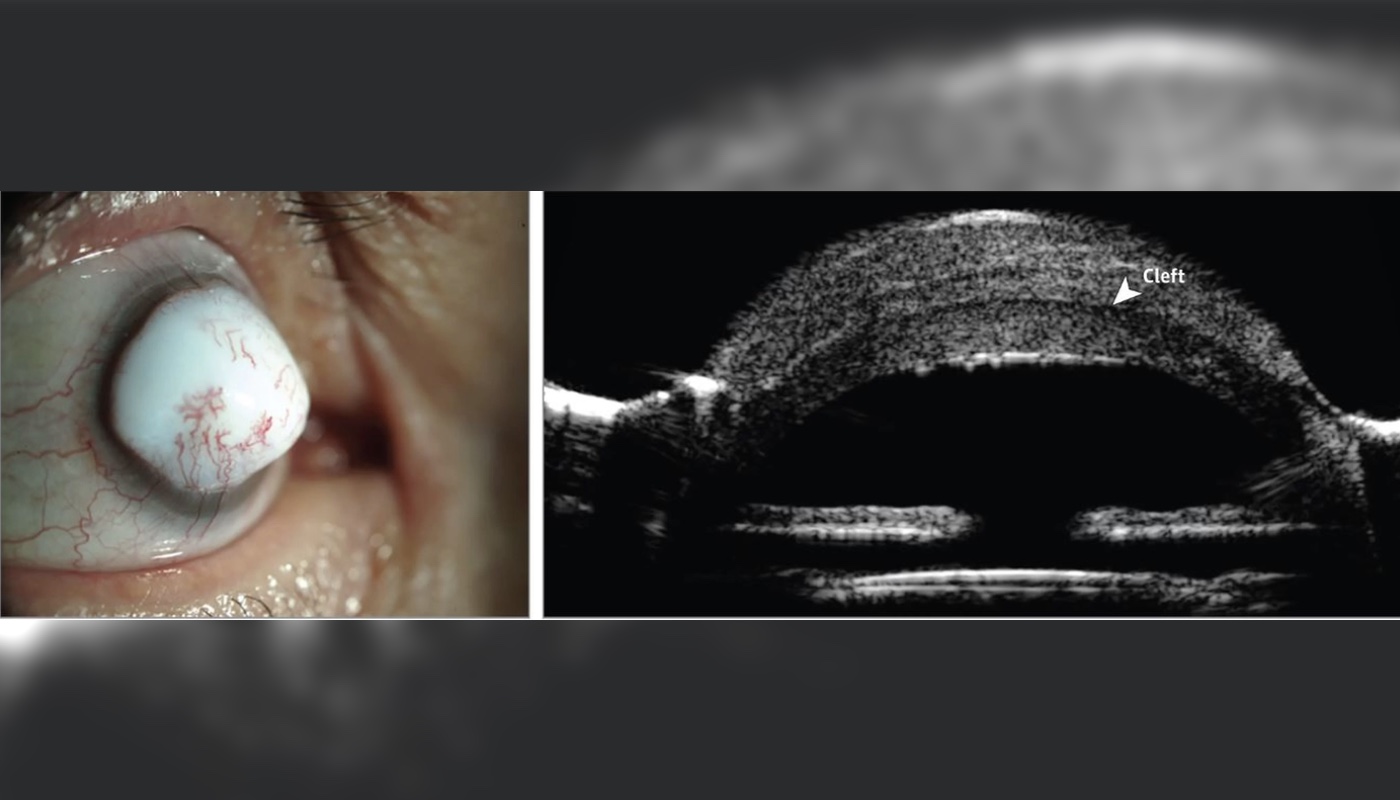

A man developed an extremely rare eye mass called a “corneal keloid” in his right eye. Above, images of the man’s eye (left), and a cross-section of the eye showing a “cleft” between the cornea and the lesion (right).

The 74 - year - old man arrived at an centre clinic with a pearly white , jelly - like great deal on his right oculus , accord to the account , published April 4 in the journalJAMA Ophthalmology . The humanity told his doctors that two years earlier , he ’d had cataract operating theatre on his right eye . after , he ’d noticed a scar on his cornea — the clean-cut , dome - shaped surface that cover the front of the eyeball — that gradually thicken over the next six months , the report say . [ ' Eye ' Ca n’t count : 9 Eyeball Injuries That Will Make You Squirm ]

Test event show that the world had a " corneal keloid , " a rarified case of wound on thecornea , according to the authors of the composition , led by Dr. Nikolas Raufi , an oculist at Duke Eye Center in Durham , North Carolina .